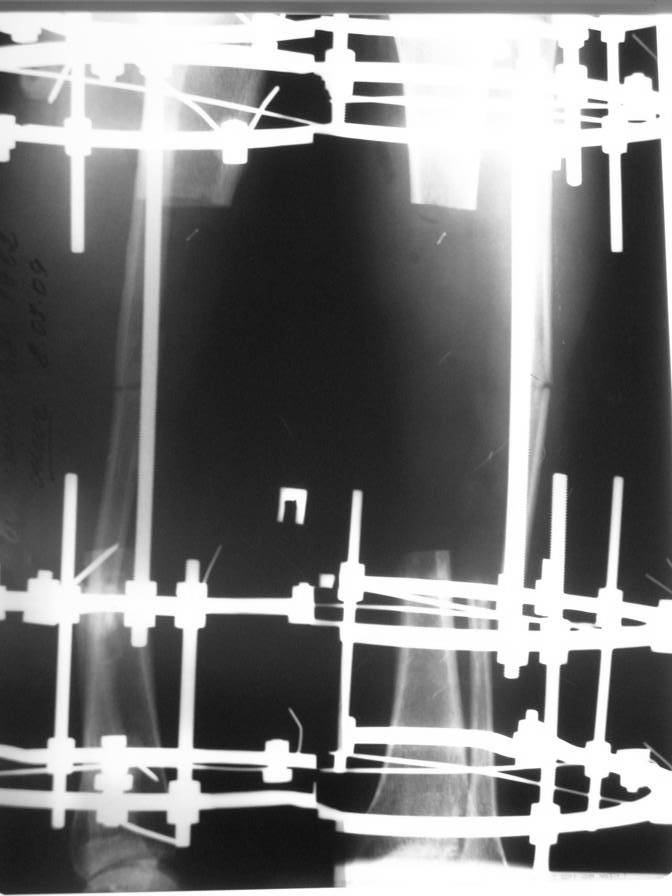

После нагноения раны металлическая пластина удалена, в рану на большом протяжении обнажилась большеберцовая кость, больной в последующем около 2-х месяцев вёлся на скелетном вытяжении, предпринимались попытки стянуть рану на передней поверхности голени местными тканями путём нанесения параллельных ране разрезов по боковой поверхности голени. К нам он поступил спустя три месяца после травмы с гнойной раной на передней поверхности голени, в которой была обнажена на большом протяжении тусклая большеберцовая кость.На операции в костно-мозговом канале большеберцовой кости гной, кость тусклая. Была произведена резекция участка большеберцовой кости длиной 17 см, пластика дефекта мягких тканей переденей поверхности голени передней большеберцовой мышцей, которой так же укрыт верхний и нижний отрезки большеберцовой кости, мышца закрыта расщеплёнными кожными лоскутами, кости голени фиксированы в аппарате Иллизарова. Послеоперационный период протекал без осложнений, все лоскуты прижились, мелкие раны зажили рубцеванием, воспаления мягких тканей вокруг спиц нет.

Недавно оперирован повторно- малоберцовая кость пересечена на уровне верхнего и нижнего отрезков большеберцовой кости, перемещена на область дефекта большеберцовой кости, фиксирована в аппарате. Рентгенснимки и фото голени больного прилагаю.

Послеоперационный период протекал без осложнений, раны зажили, швы сняты, больной ходит с полной опорой на ногу в аппарате, воспаления мягких тканей вокруг спиц нет. Планируется постепенное увеличение нагрузки на перемещённую малоберцовую кость путём этапного удаления спиц под рентген контролем.